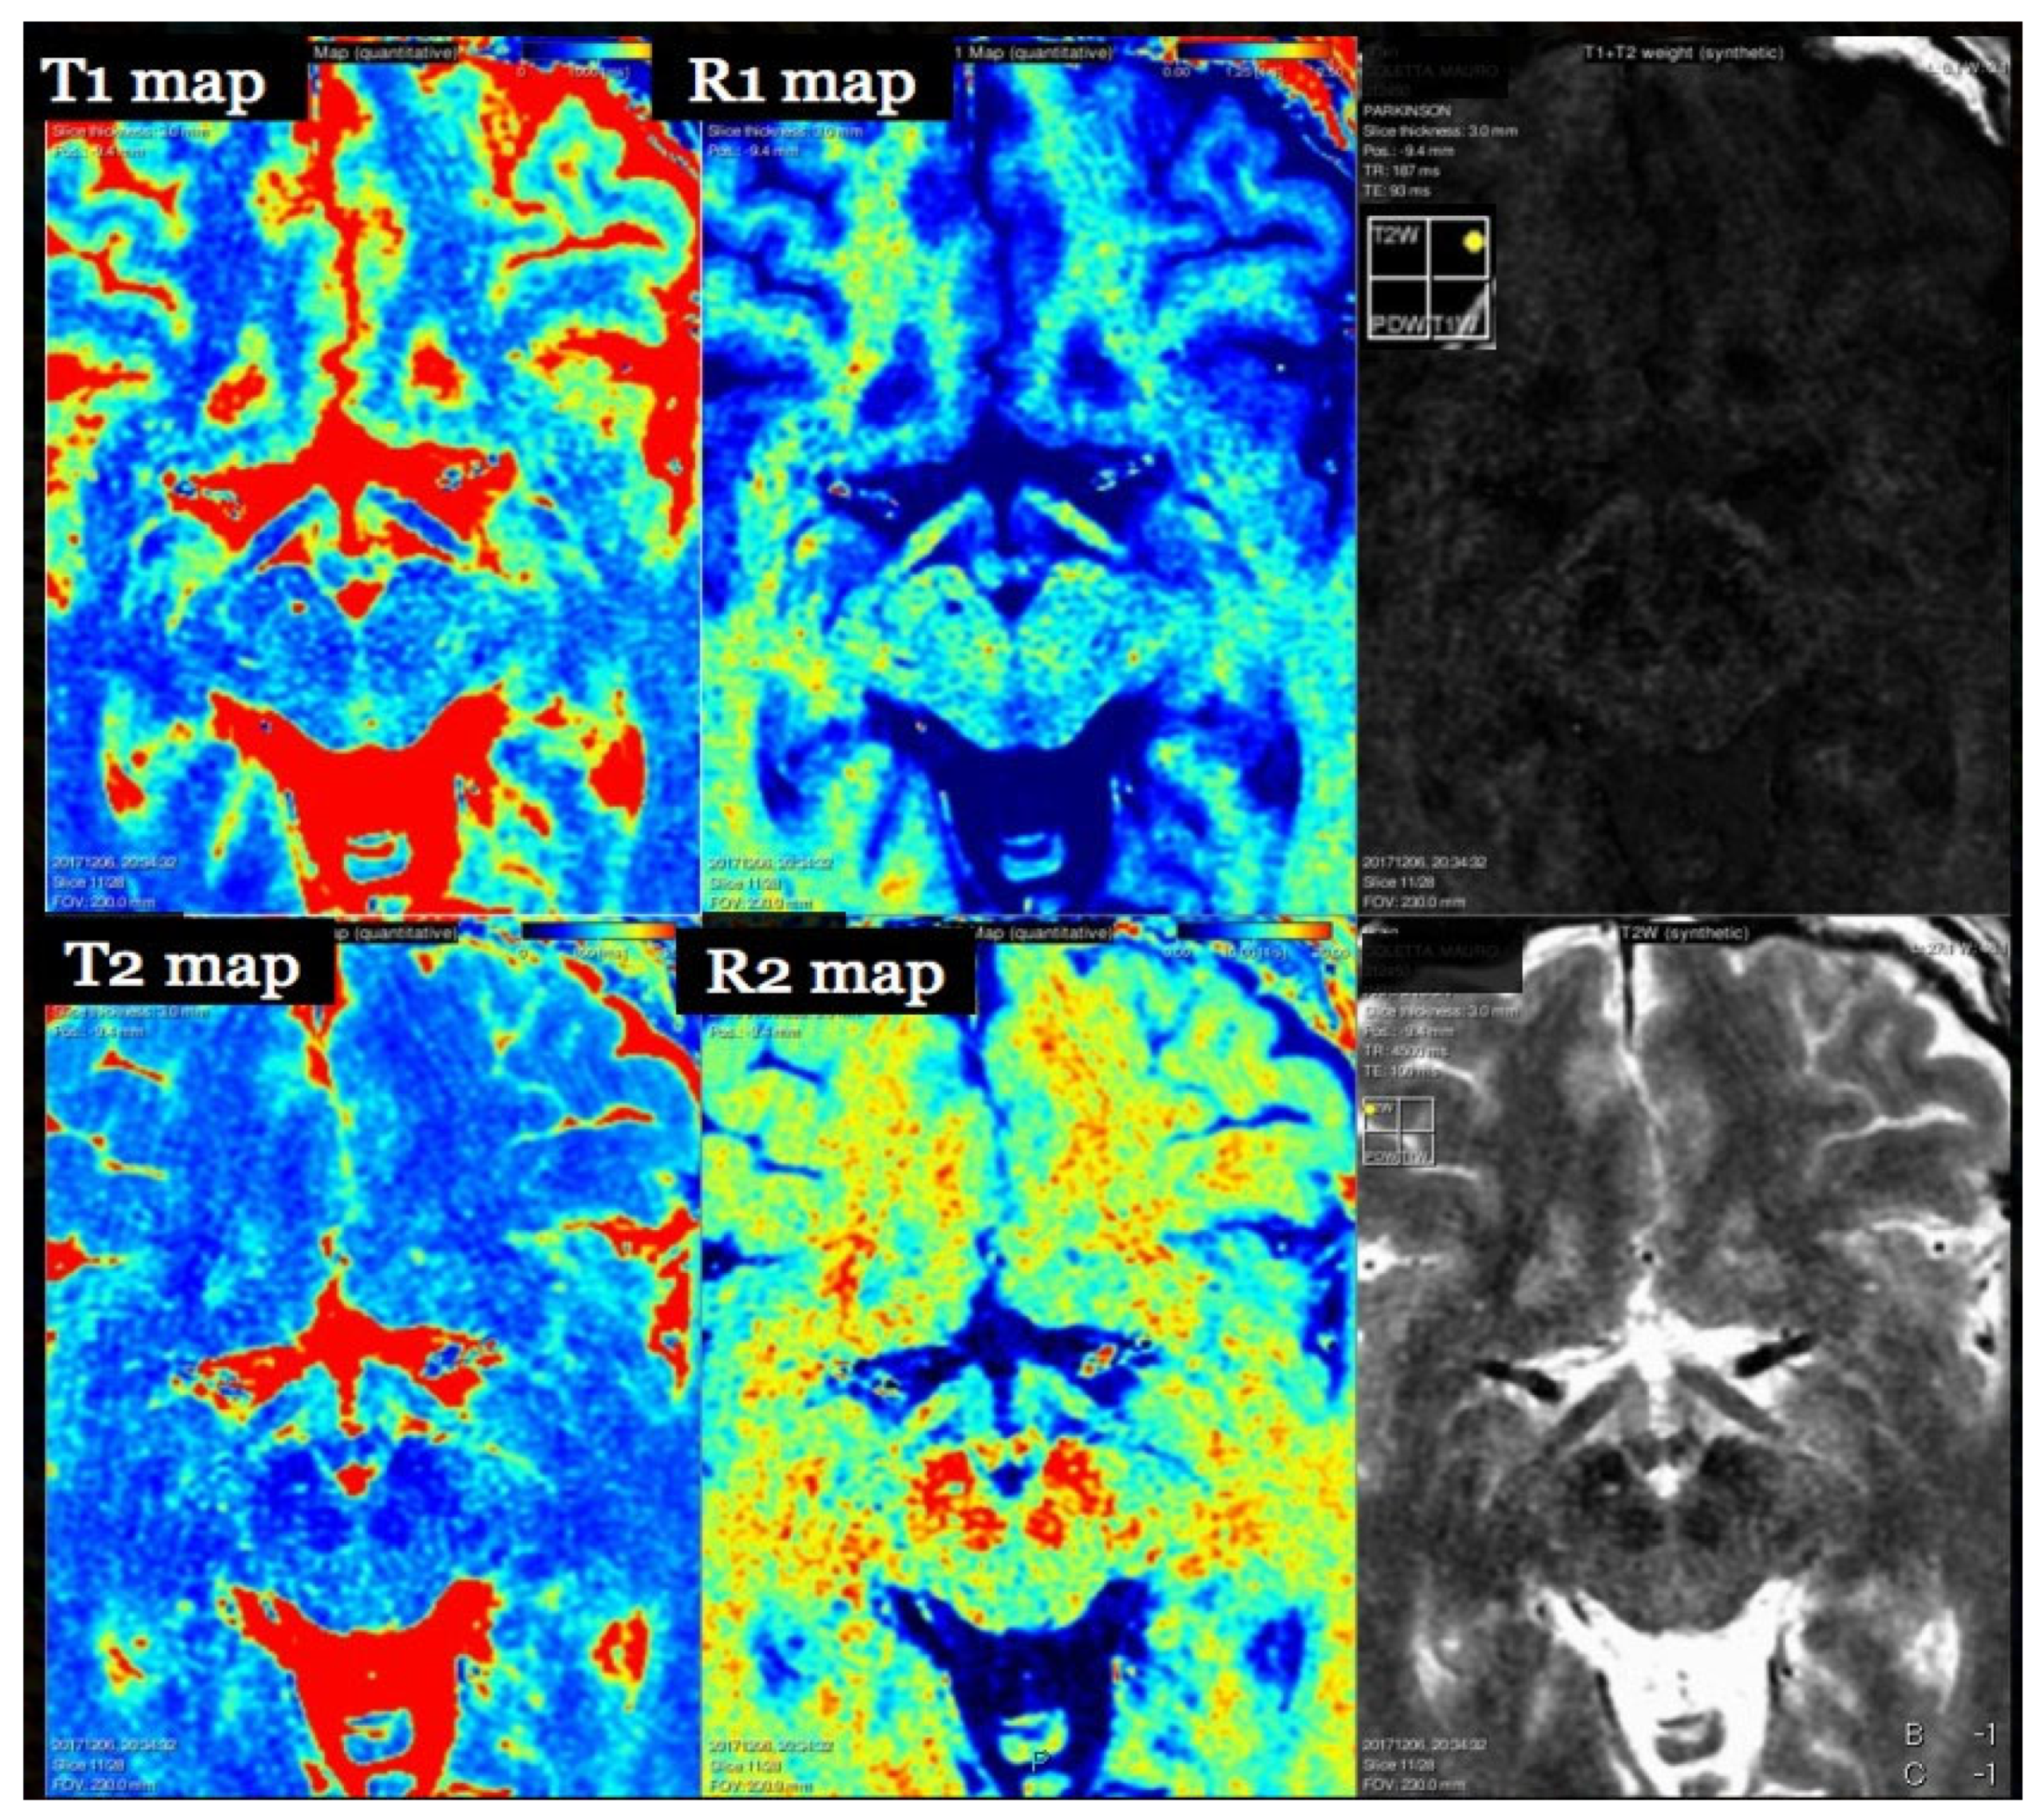

7. T1 Relaxometry

8. T2 Relaxometry and Magnetization Transfer

- Hagiwara, A.; Warntjes, M.; Hori, M.; Andica, C.; Nakazawa, M.; Kumamaru, K.K.; Abe, O.; Aoki, S. SyMRI of the Brain. Investig. Radiol. 2017, 52, 647–657. [Google Scholar] [CrossRef]

- Tanenbaum, L.; Tsiouris, A.; Johnson, A.; Naidich, T.; DeLano, M.; Melhem, E.; Quarterman, P.; Parameswaran, S.; Shankaranarayanan, A.; Goyen, M.; et al. Synthetic MRI for Clinical Neuroimaging: Results of the Magnetic Resonance Image Compilation (MAGiC) Prospective, Multicenter, Multireader Trial. Am. J. Neuroradiol. 2017, 38, 1103–1110. [Google Scholar] [CrossRef]